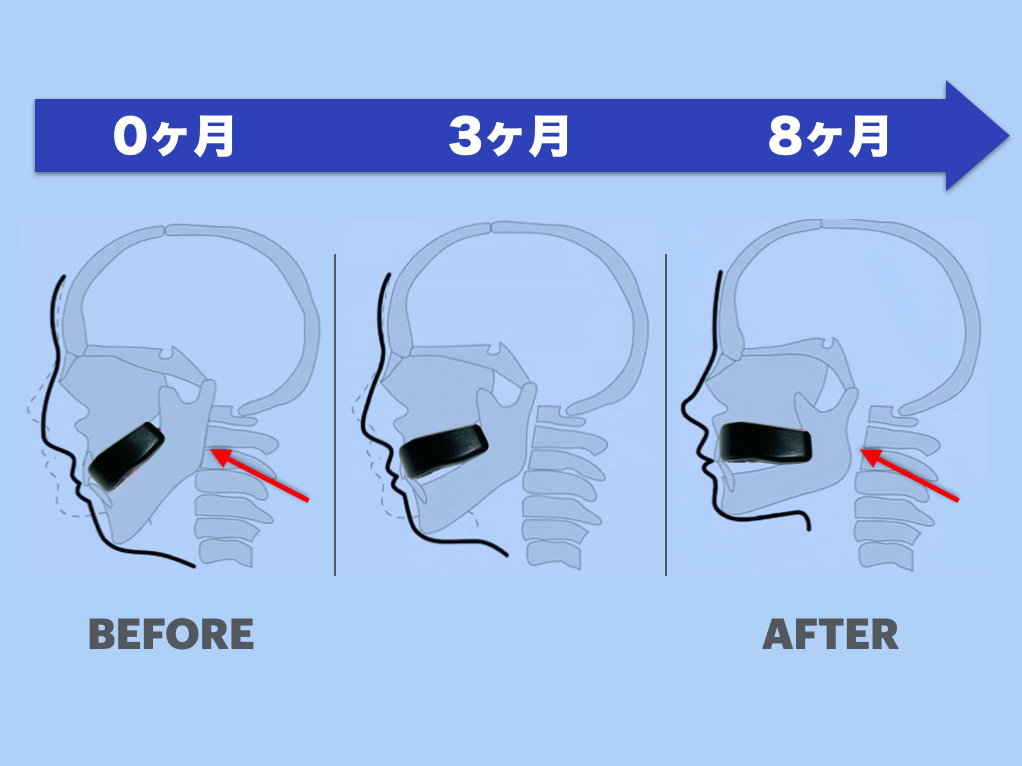

骨の再構築(リモデリング)作用

さつま式小顔マウスピースの効果は「その場しのぎ」ではありません。長期的に顎位を改善し、「骨そのものの構造」を変える可能性があります。

- さつま式小顔マウスピースにより新しい顎の位置で日常的に会話や咀嚼を行う

- 顎関節や周囲の骨・靭帯・筋肉に継続的な刺激が加わる

- → その結果、骨密度や形状が変化=顎の回転中心が“骨ごと”適応していく

特に若年者や、可塑性が残っている高齢者において、この作用は重要です。

さつま式小顔マウスピースによる顎位の是正は、中長期的に全身の健康バランスを支える一手となります。